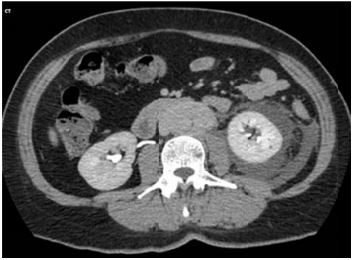

Mulher, 45 anos, apresenta dor abdominal progressiva há 4 meses e edema de membros inferiores há três semanas. Antecedentes pessoais: tireoidectomia por bócio há 6 anos. Anatomopatológico tireoide: fibrose extensa. Medicamentos em uso: levotiroxina 75mcg/dia. Exame físico: PA 152/99mmHg, FC 92 bpm, edema (2+/4) de membros inferiores. Ausculta cardiopulmonar normal. Exames laboratoriais: creatinina 2,4mg/dL; exame de urina: proteína ausente, hemácias 4/campo, leucócitos 12/campo. Tomografia computadorizada de abdome:

Imagem abaixo.

A hipótese diagnóstica e conduta são: